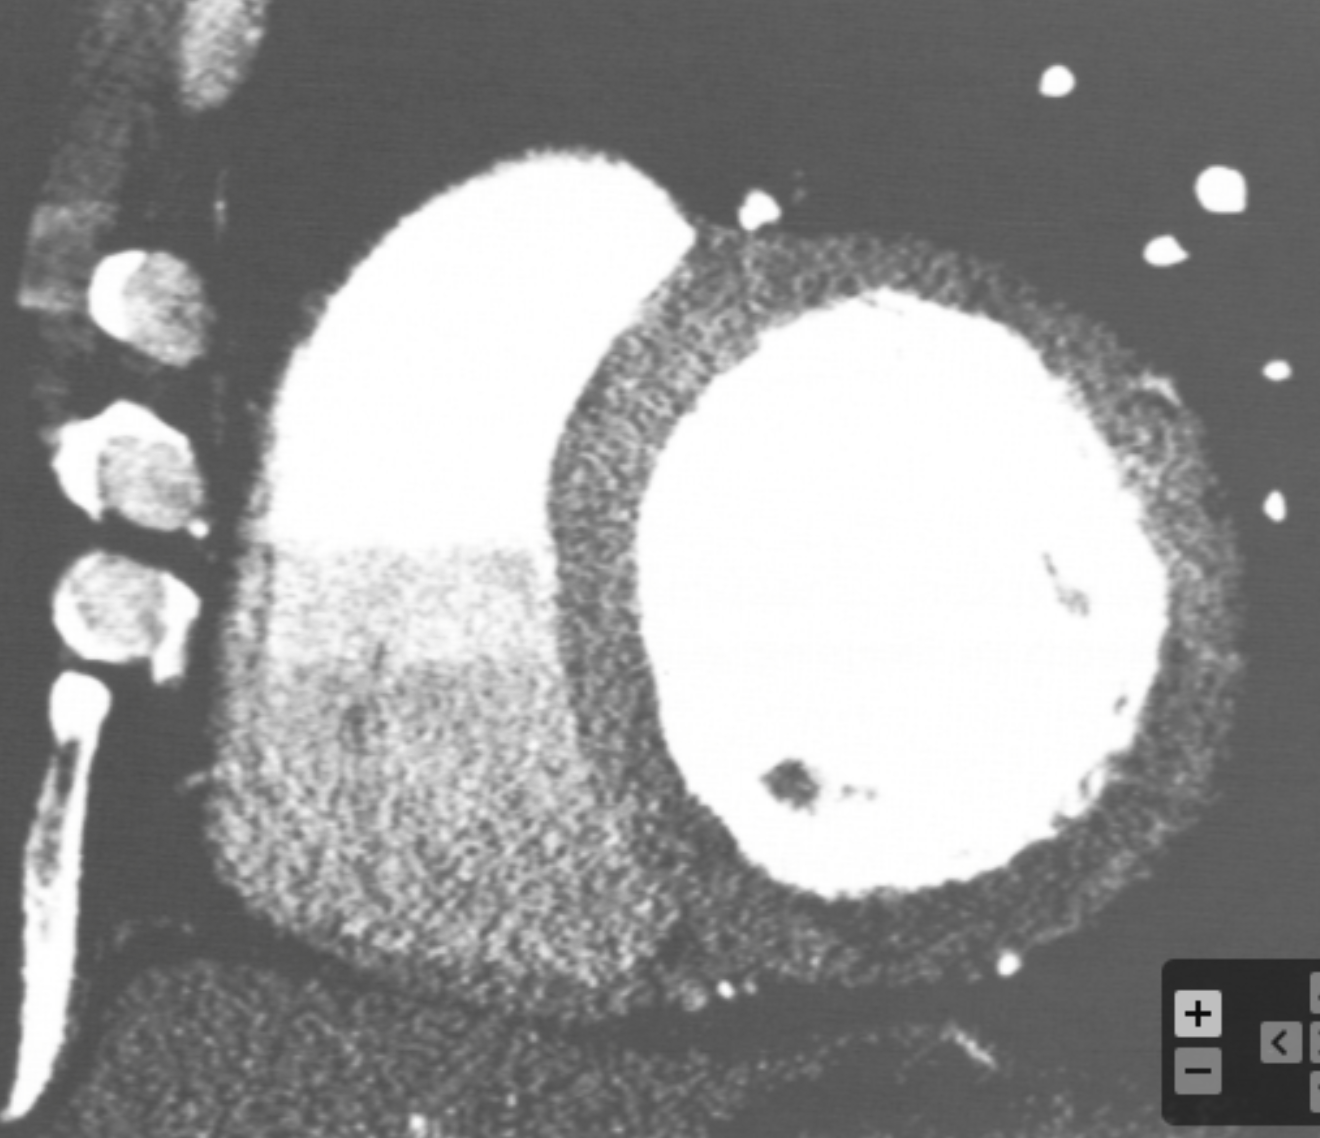

How can a myocardial perfusion defect be differentiated from an artifact?

Which are the best window width and window level for assessing myocardial perfusion defects, respectively?

WW: 200 / WL: 100

Which coronary artery distribution is affected by the perfusion defect displayed in the image?

LCx or RCA (depending on dominance)